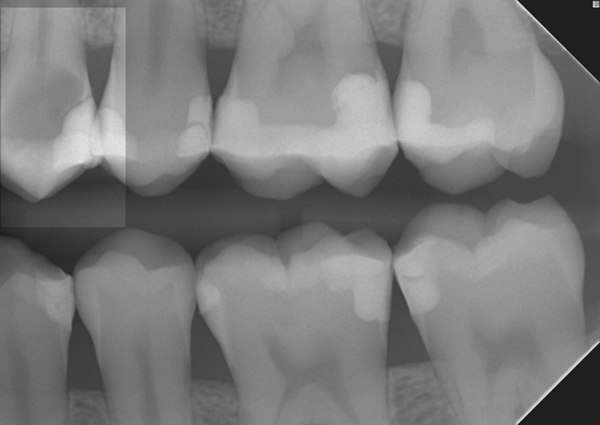

Im Röntgenbild wird das Ausmaß der kariösen Zerstörung der Zahnkrone deutlich. Bissflügelaufnahme links: